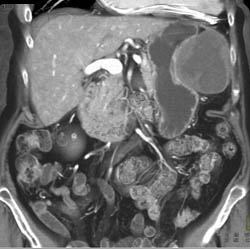

GIST Tumor